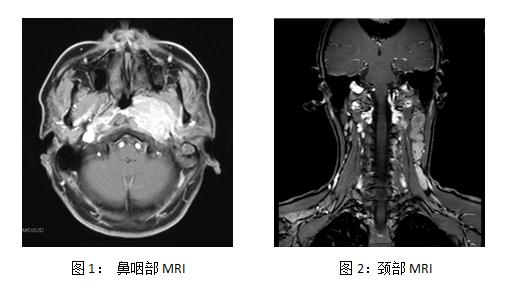

鼻咽及颈部MRI示(下图1, 2):鼻咽左侧见约3.9 × 3 × 3.6 cm3稍长T1,T2信号占位,左侧咽鼓管咽口、咽隐窝、圆枕结构显示不清,咽旁间隙受累,左侧颈内动脉受包绕,左侧头长肌、斜坡、岩尖、翼突根部、海绵窦受累 (图1未显示)。左侧咽旁间隙、劲动脉鞘区及颈后三角淋巴结增多、增大、融合,最大约6.8 × 4.3 cm,增强明显、不均匀强化。